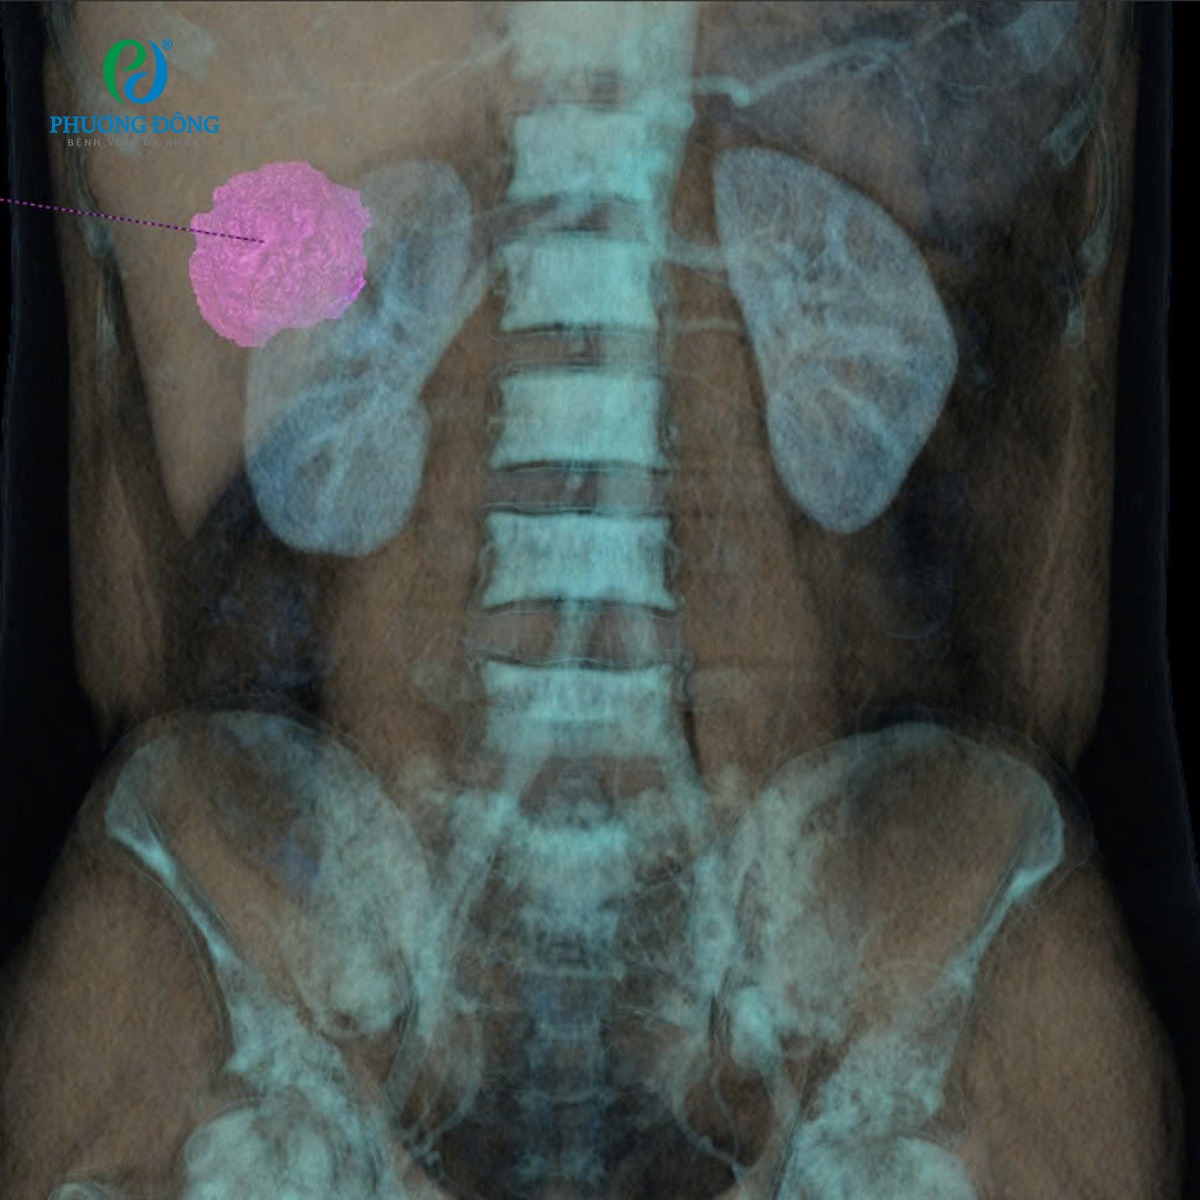

Kết quả chụp CT Photon – công nghệ chẩn đoán hình ảnh hiện đại hàng đầu tại Bệnh viện Đa khoa Phương Đông phát hiện:

- Khối u cơ mỡ mạch (AML) thận phải, kích thước khoảng 5 cm

- Bên trong u xuất hiện ổ giả phình động mạch đường kính 6 mm

Nhận định đây là trường hợp có nguy cơ chảy máu lớn, các bác sĩ Khoa Chẩn đoán hình ảnh - Can thiệp điện quang đã quyết định lựa chọn phương pháp nút mạch chọn lọc để bảo tồn tối đa thận lành, thay vì phẫu thuật cắt thận. Dưới gây tê tại chỗ, bác sĩ tiến hành: